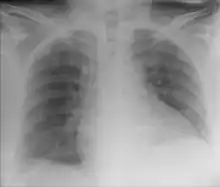

![]() | |

| Chest X-ray showing obvious Chilaiditi's sign, or presence of gas in the right colic angle between the liver and right hemidiaphragm. | |